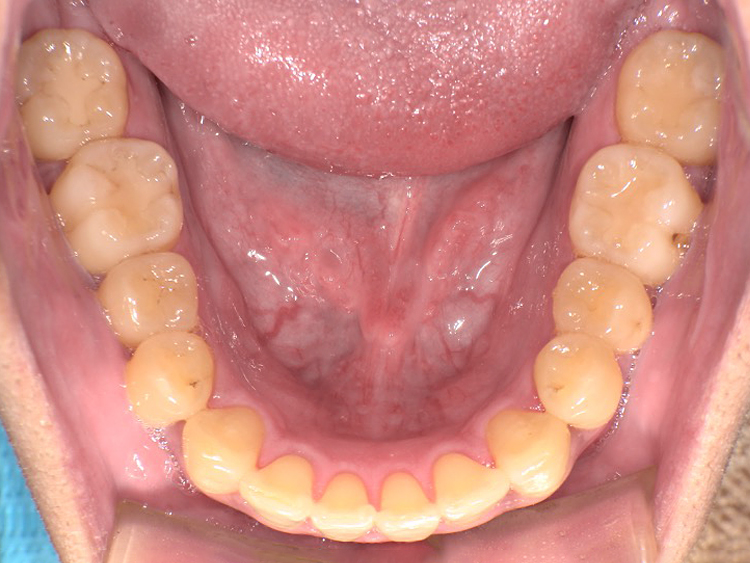

症例6

Before

After

| 主訴 | 噛み合わせが気になる |

|---|---|

| 年齢 | --- |

| 治療 期間 |

約2年11ヶ月 |

| 治療 内容 |

インビザラインコンプリヘンシブ 右上6番・左上6番ALLセラミッククラウン |

| 治療費 | ¥1,116,000(税込)/調整料含む |

| 治療のリスク | 歯を動かすことで、歯茎が下がるリスクある。 矯正終了後は、リテーナーを使用し、後戻りを防ぐ必要がある。 |